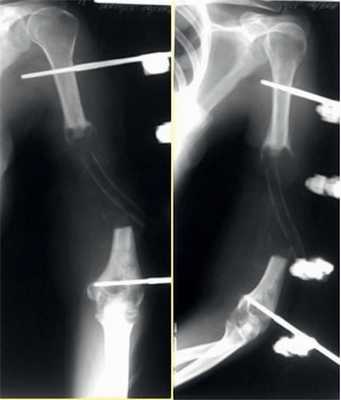

На рис. 10-14 Рис. 10. Рентгенограмма пациентки Н. до операции. Рис. 14. Внешний вид и функция пациентки Н. через 8 мес после операции. представлены этапы обследования и лечения пациентки Н.

Рис. 11. Пациентка Н. Оперативное лечение: резекция зоны ложного сустава левой плечевой кости, остеосинтез пластиной и винтами. Пластика свободным кровоснабжаемым трансплантатом из внутреннего мыщелка бедренной кости.

Рис. 12. Рентгенограммы пациентки Н. после операции.

Рис. 13. Рентгенограммы пациентки Н. через 8 мес после операции.